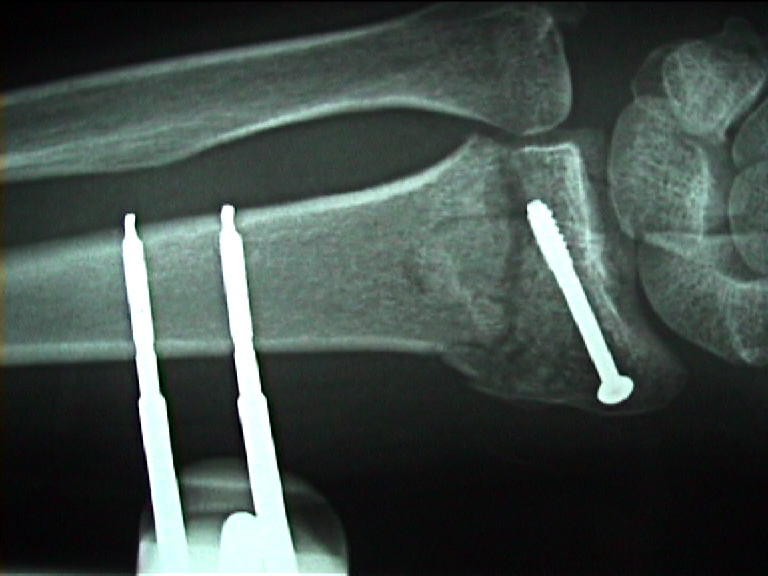

Arztbrief